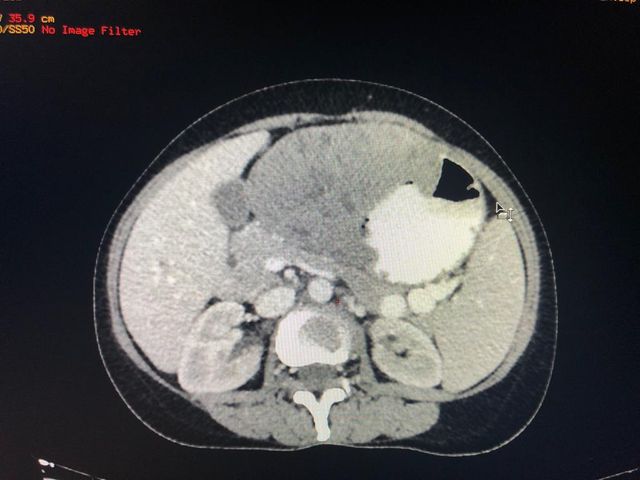

A rare case of gastric schwannoma masquerading as a GIST - 52 year old lady presented with massive GI bleed

A rare case of gastric schwannoma masquerading as a GIST. 52 year old lady presented with massive GI bleed and severe anemia Hb 5.0 gm. Her CT scan and endoscopy revealed a exophytic lesion 10 x 12 cmof gastric body with a ulceration in stomach. She underwent a lap assisted subtotal gastrectomy with a diagnosis of a GIST. Post operative immunohistochemistry revealed a gastric schwannoma. Gastric schwannoma is a very rare mesenchymal tumor arising from the nerve plexus of gastric wall . Unlike gastric GIST of this size >10 cm which are usually the rare malignant schwannoma are entirely benign with excellent long term prognosis.